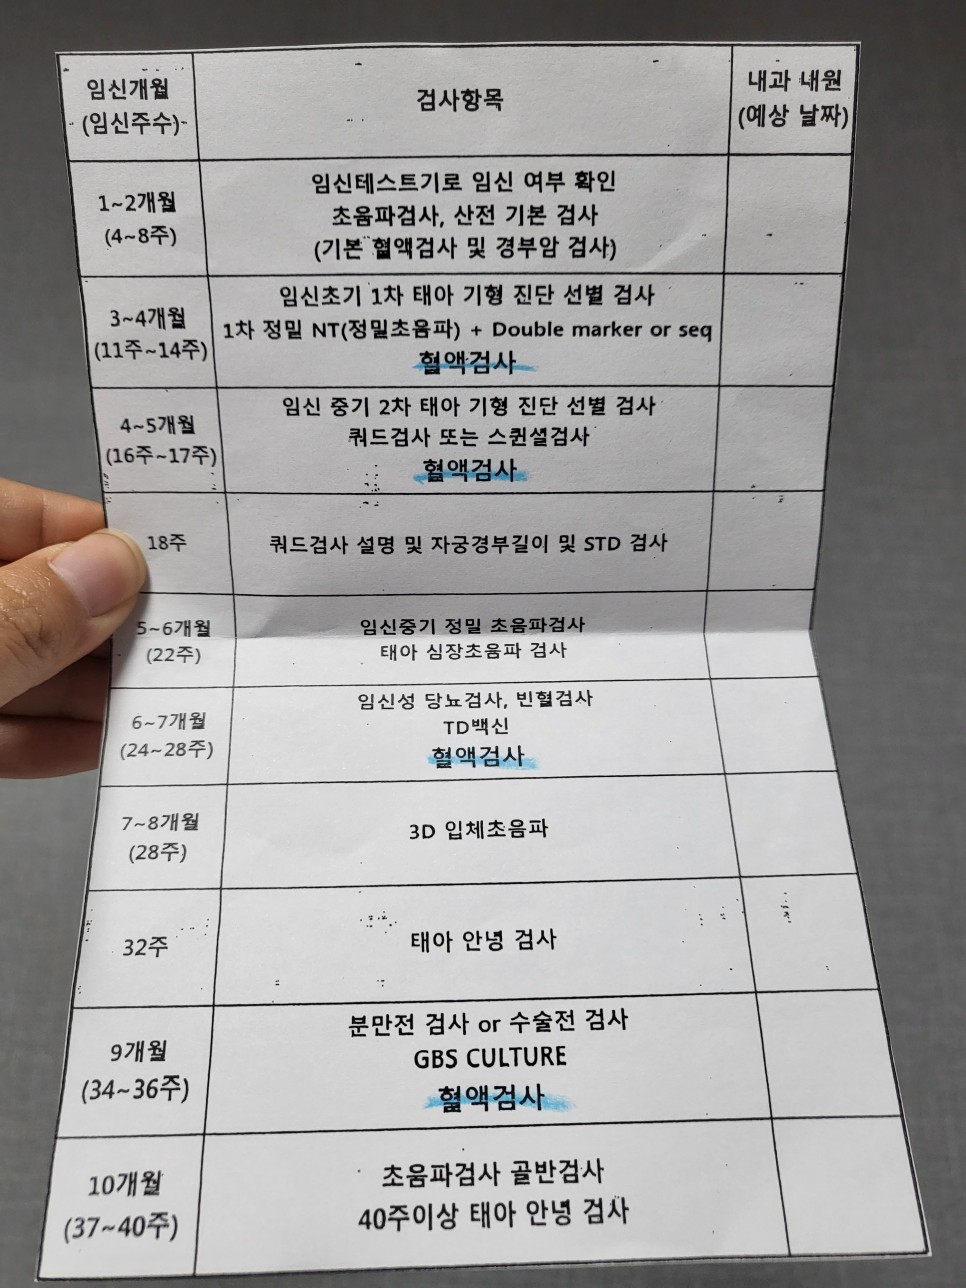

다음 진료는 12주에 1차 기형아 검사로 정밀 초음파실에 NT 검사를 예약했다.

산전검사에서 처음 수치를 확인하고 1개월 후 12주차, 1차 기형아 검사 시 재검, 1개월 후 16주차, 2차 기형아 검사 시 재검.이렇게 내분비내과 혈액검사 일정표를 받았다.